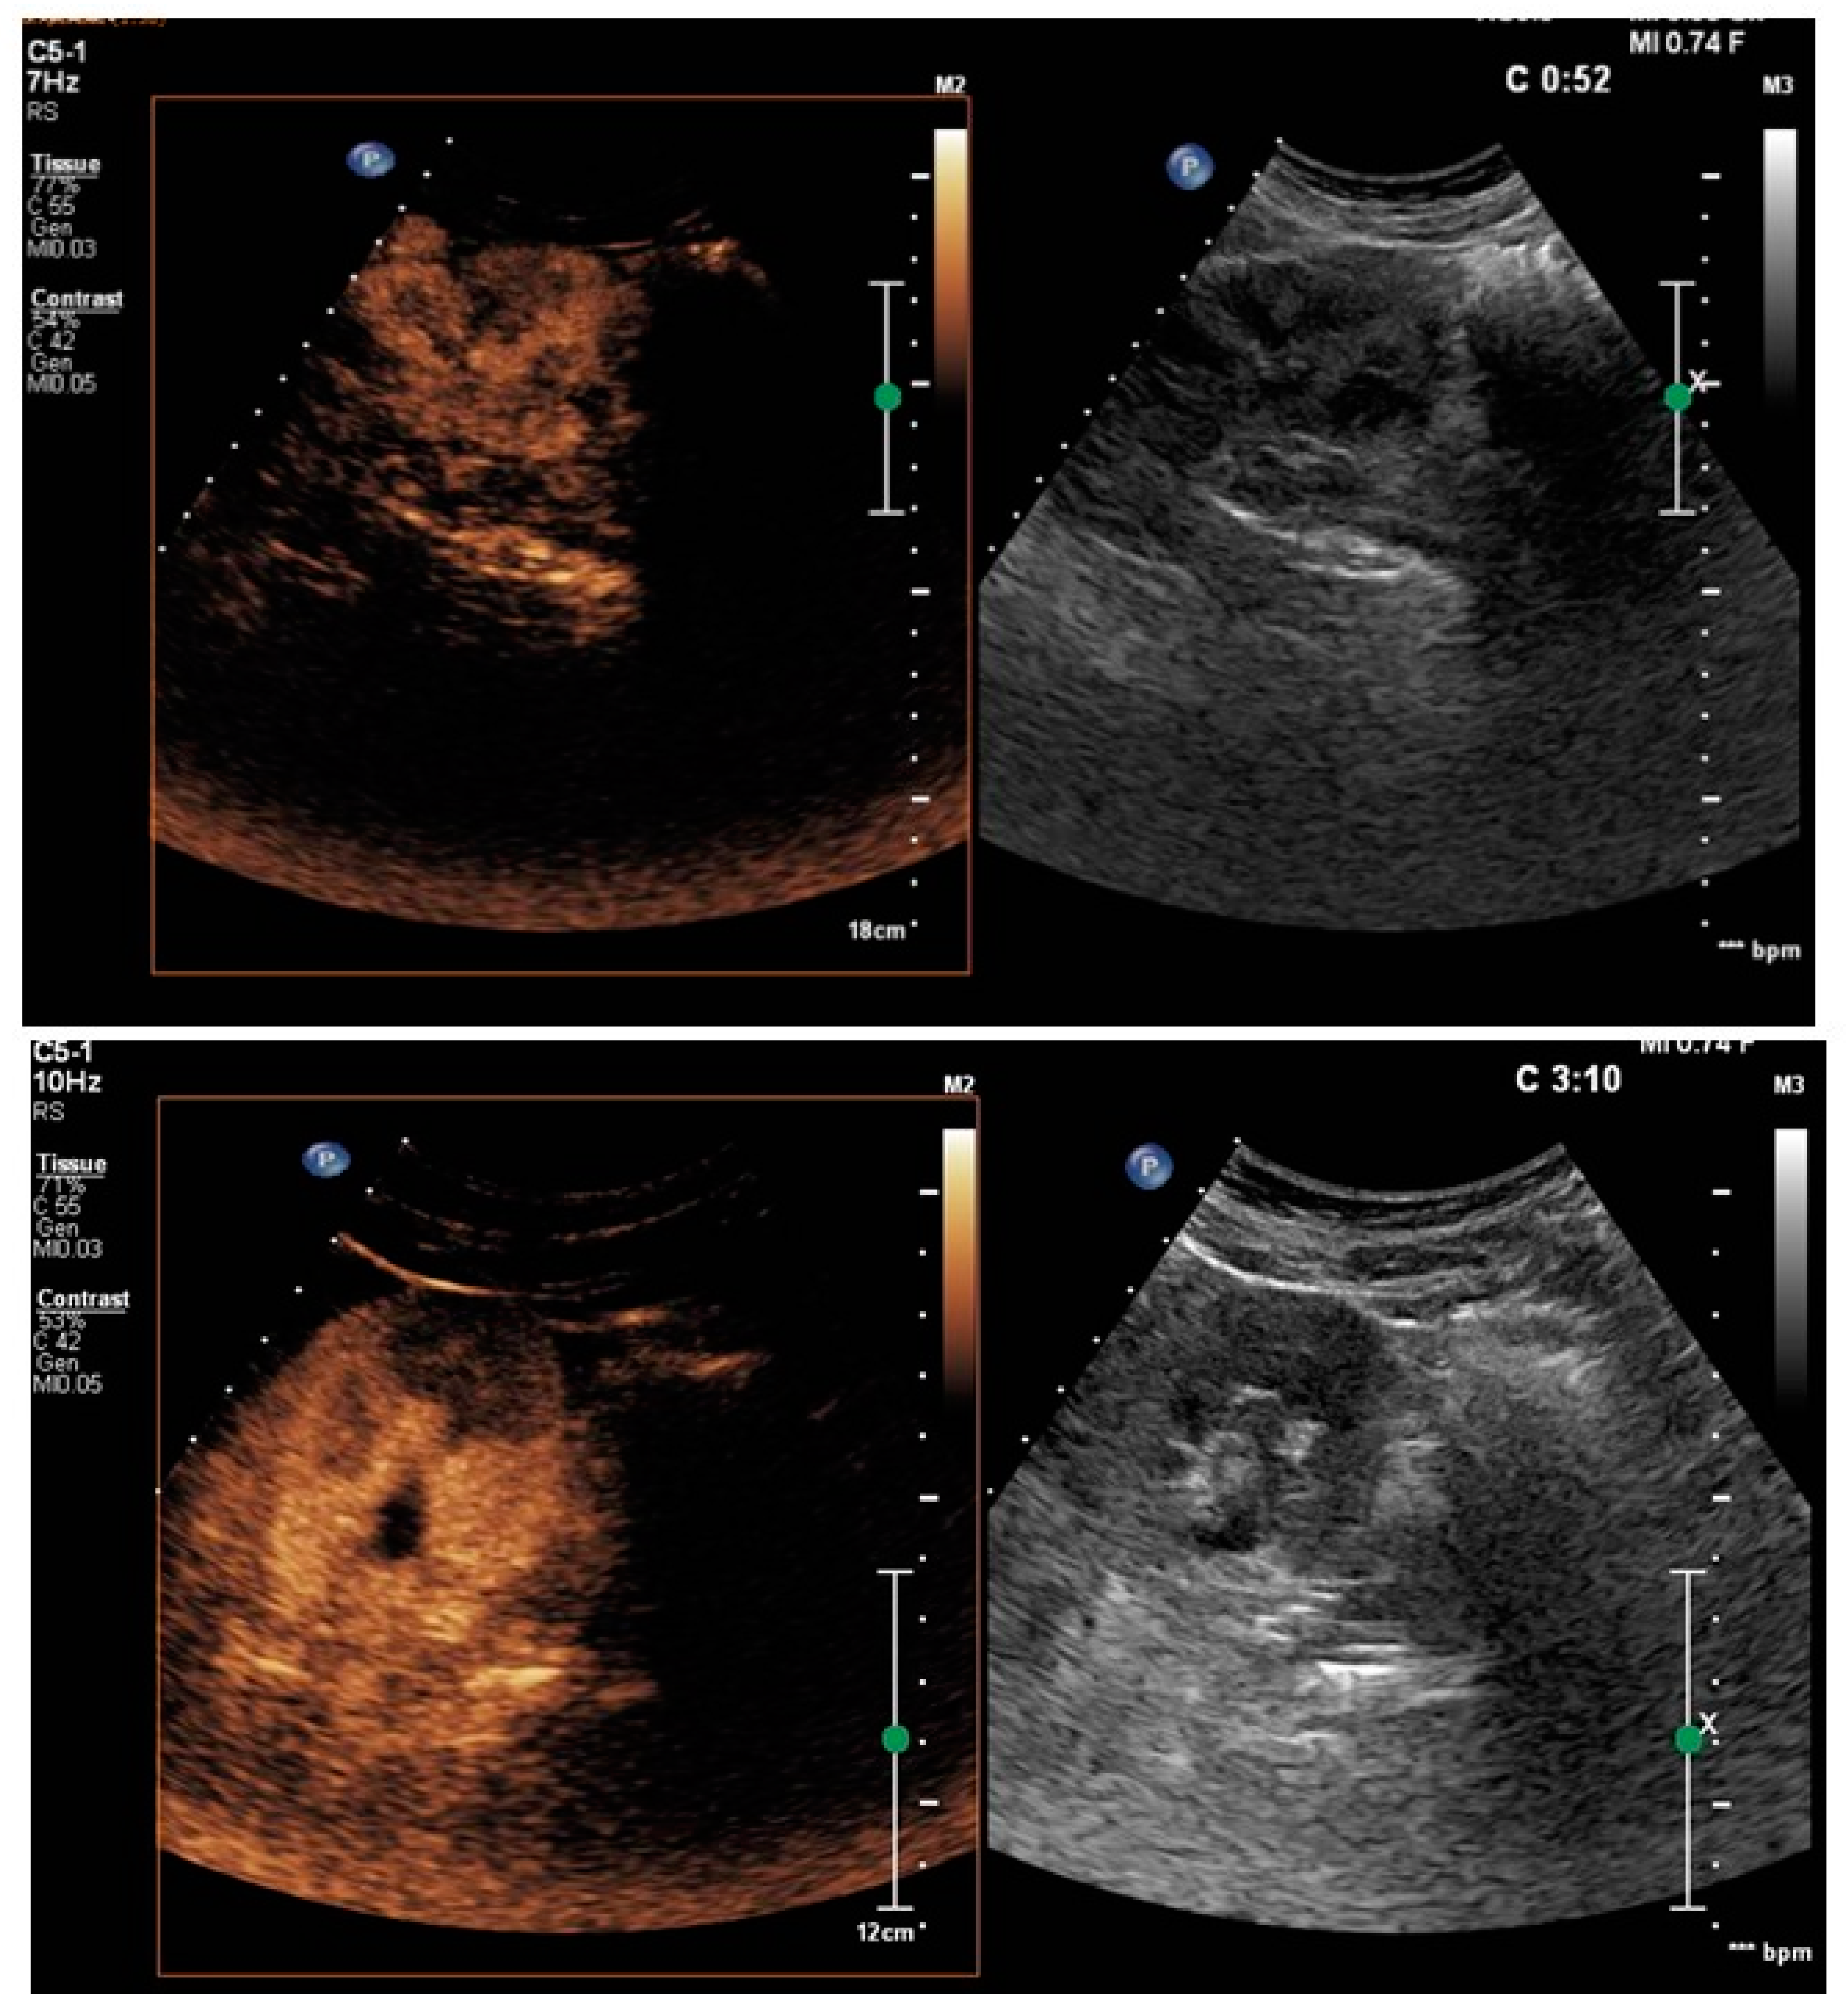

- Rinaldo, C.; Grimaldi, D.; Di Serafino, M.; Iacobellis, F.; Verde, F.; Caruso, M.; Sabatino, V.; Orabona, G.D.; Schillirò, M.L.; Vallone, G.; et al. An update on pyelonephritis: Role of contrast enhancement ultrasound (CEUS). J. Ultrasound 2023, 26, 333–342. [Google Scholar] [CrossRef]